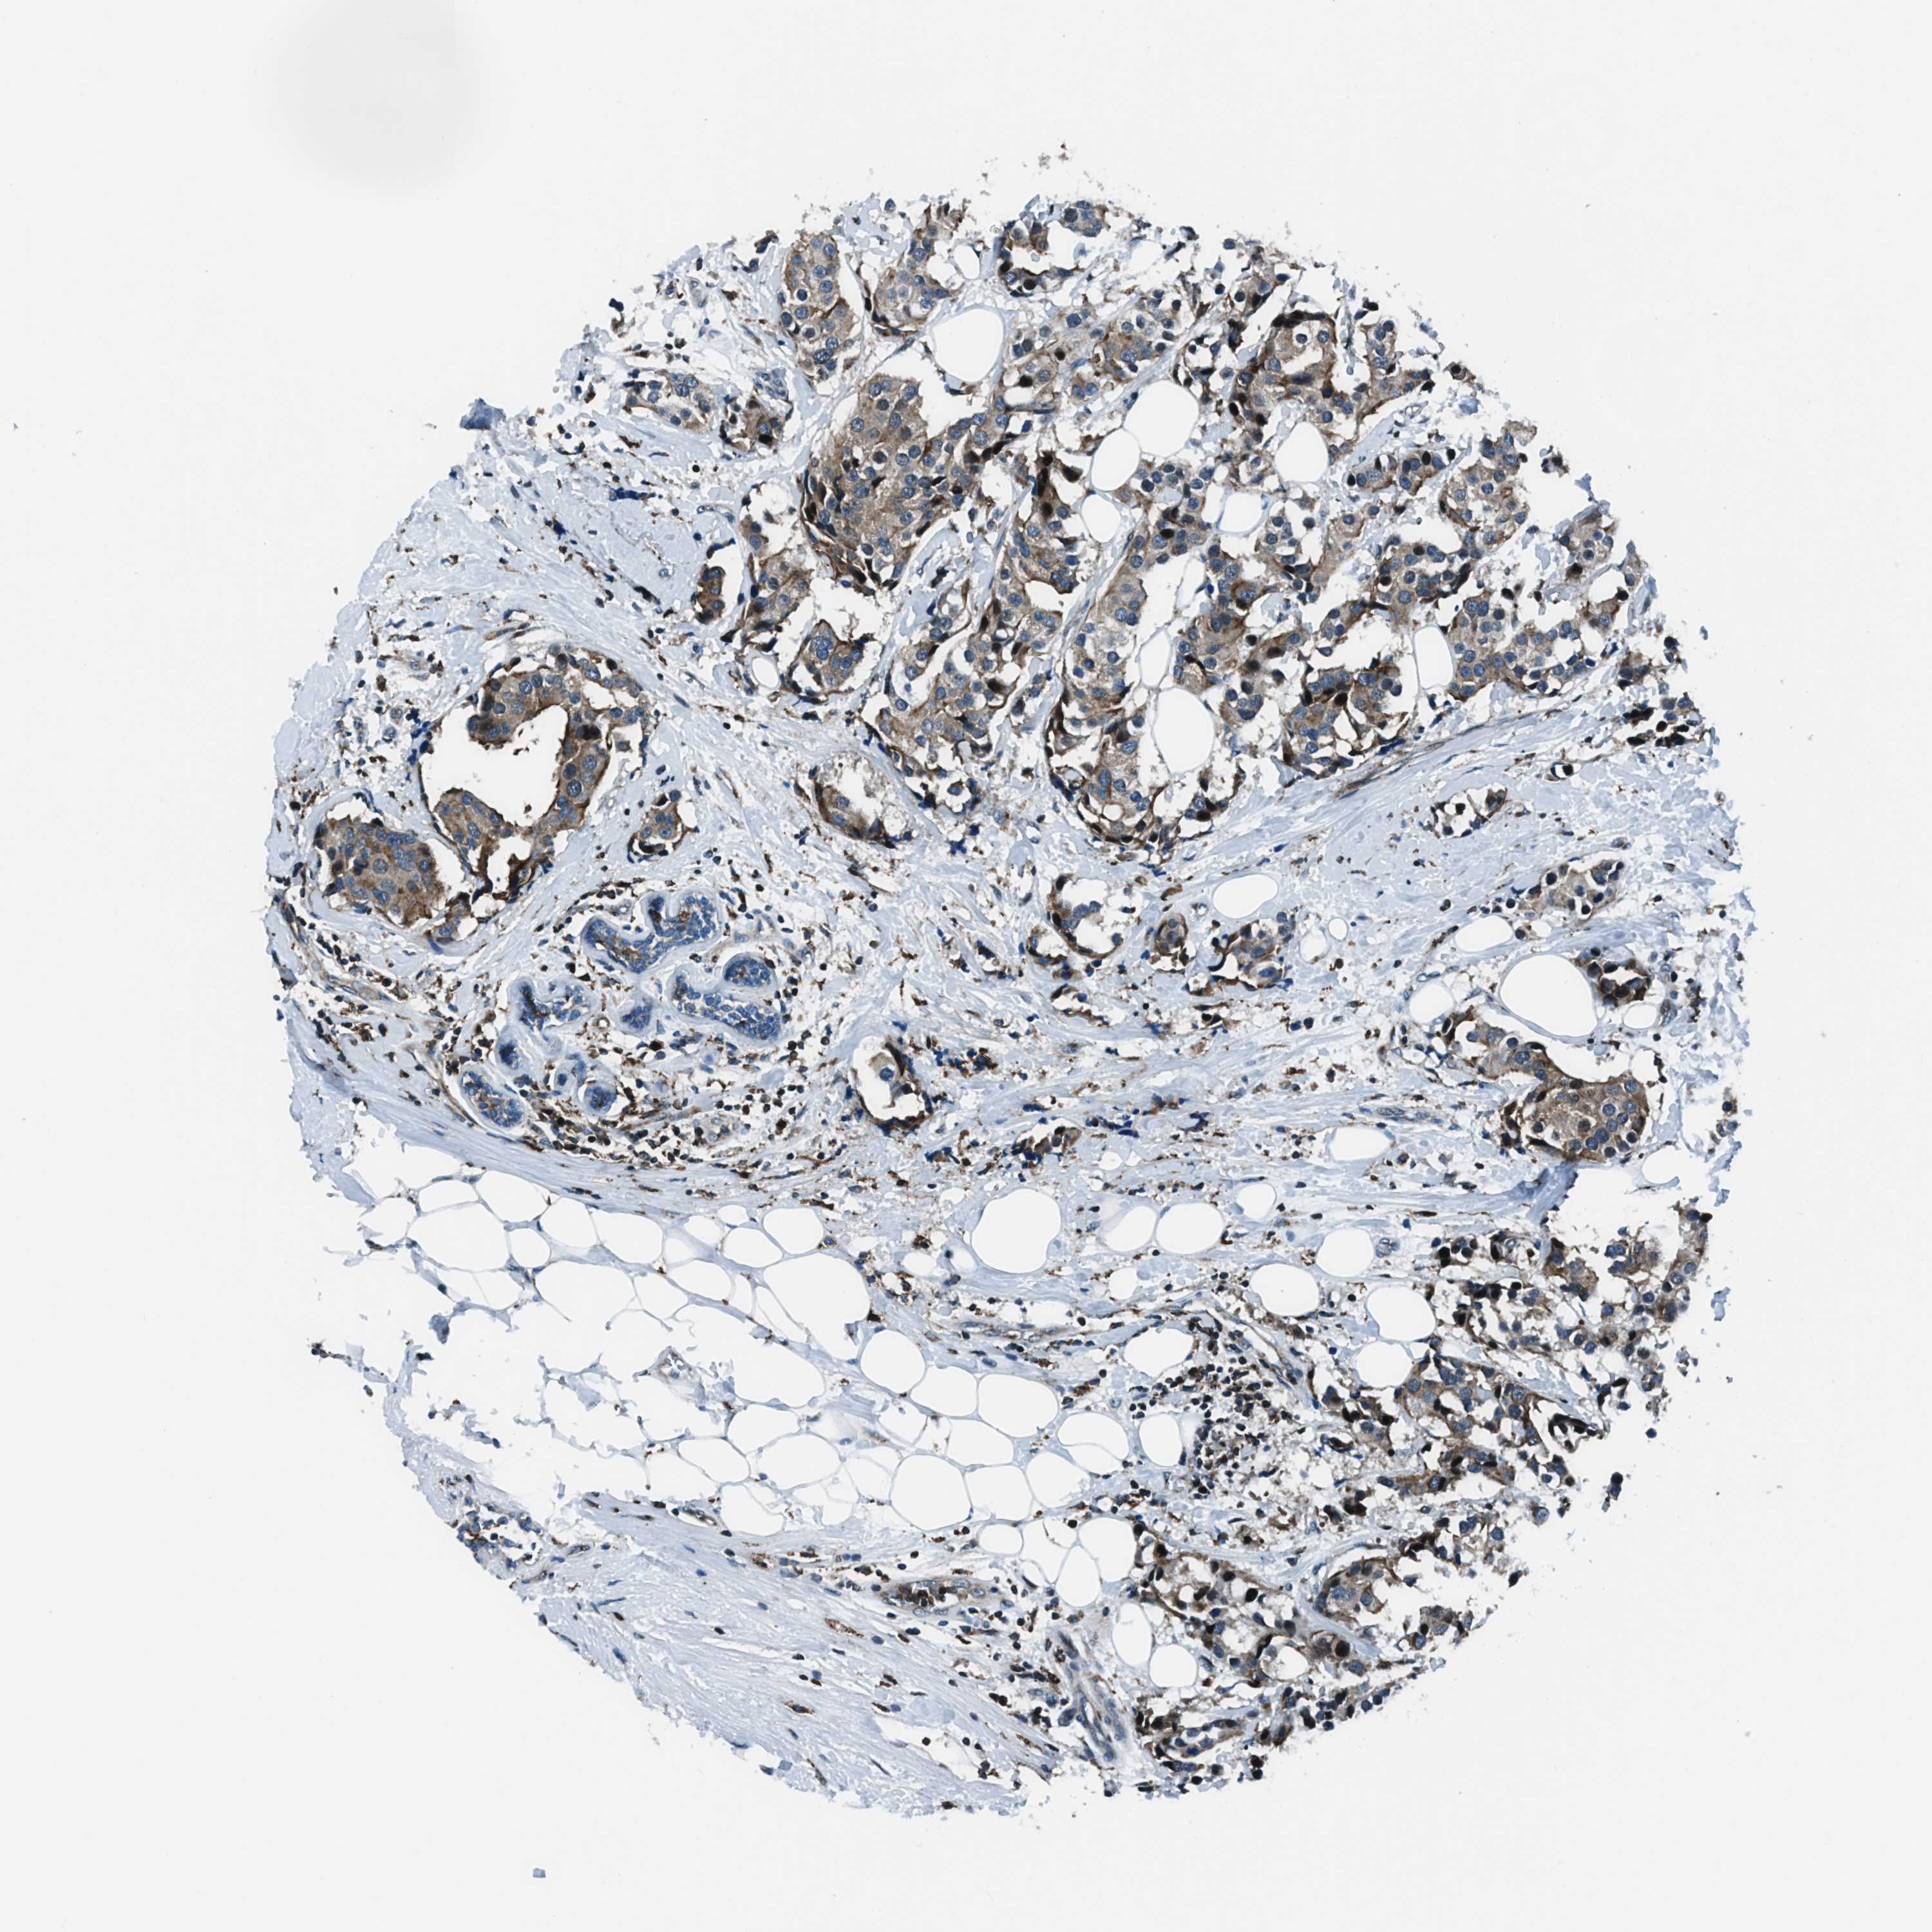

CANCER BREAST CANCER Show tissue menu

BRCA TCGA BRCA VALIDATION PROTEIN EXPRESSION